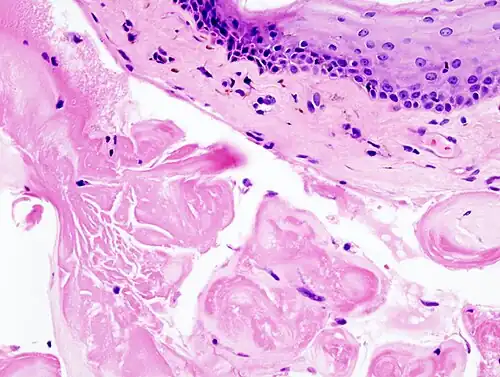

Guzki głosowe występują na granicy 1/3 przedniej i środkowej części fałdów głosowych. Ich wielkość nie przekracza wielkości łebka od szpilki. Mają stożkowaty kształt i są jednakowej wielkości. Zdarza się rzadko, że mogą one występować pojedynczo lub że na jednej strunie jeden guzek śpiewaczy jest większy. Umiejscowione są na wolnym brzegu fałdu głosowego w jego górnej części. Pokryte są złogami nawarstwionego nabłonka wielowarstwowego płaskiego, który spoczywa na bezpostaciowej i pogrubiałej łącznotkankowej podstawie. Na obwodzie obserwuje się niewielkie nacieki z komórek zapalnych.